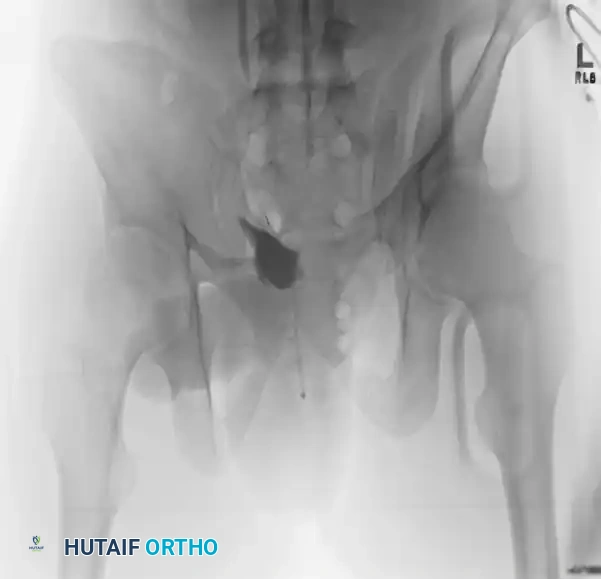

Case 1: Young-Burgess Anteroposterior Compression Type II (AP II)

An AP II injury is characterized by an "open book" pelvis. The mechanism is a direct anterior-to-posterior force causing symphyseal diastasis (>2.5 cm) and disruption of the anterior sacroiliac, sacrotuberous, and sacrospinous ligaments. The posterior sacroiliac ligaments remain intact, preventing vertical translation but allowing rotational instability.

Preoperative Evaluation:

The preoperative AP view demonstrates significant widening of the symphysis pubis.

FIGURE 56-43: Young and Burgess anteroposterior type II (AP II) pelvic ring injury with pubic diastasis treated with anterior fixation. A and B, Preoperative views. C-E, Postoperative anteroposterior, inlet, and outlet views.